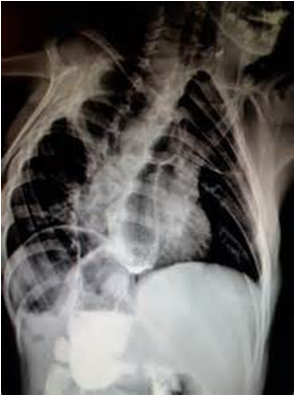

2.颈、胸、腹正侧位X线摄片示导管卷曲或造影显示食道近端盲袋。